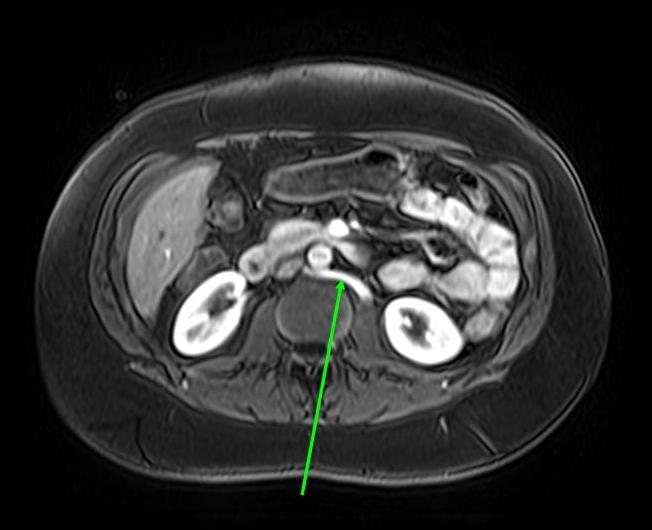

Nutcracker Morphology . nutcracker syndrome, or left renal vein entrapment, describes an uncommon condition involving compression of the left. nutcracker syndrome (ncs) is a syndrome caused by compression of the left renal vein (lrv), between the abdominal. nutcracker syndrome (ncs) is an extrinsic compression of the left renal vein (lrv) by the superior mesenteric artery. the nutcracker phenomenon, also known as nutcracker anatomy or left renal vein entrapment, refers to the anatomic or pathophysiologic entity wherein the superior. most typical nutcracker morphologic features imply compression of the lrv between the aorta and the superior mesenteric artery (sma), known as anterior nutcracker.

Nutcracker Morphology nutcracker syndrome (ncs) is an extrinsic compression of the left renal vein (lrv) by the superior mesenteric artery. nutcracker syndrome (ncs) is an extrinsic compression of the left renal vein (lrv) by the superior mesenteric artery. the nutcracker phenomenon, also known as nutcracker anatomy or left renal vein entrapment, refers to the anatomic or pathophysiologic entity wherein the superior. nutcracker syndrome (ncs) is a syndrome caused by compression of the left renal vein (lrv), between the abdominal. most typical nutcracker morphologic features imply compression of the lrv between the aorta and the superior mesenteric artery (sma), known as anterior nutcracker. nutcracker syndrome, or left renal vein entrapment, describes an uncommon condition involving compression of the left.

Diagnostics Free FullText Anterior and Posterior Nutcracker Nutcracker Morphology nutcracker syndrome (ncs) is a syndrome caused by compression of the left renal vein (lrv), between the abdominal. most typical nutcracker morphologic features imply compression of the lrv between the aorta and the superior mesenteric artery (sma), known as anterior nutcracker. nutcracker syndrome, or left renal vein entrapment, describes an uncommon condition involving compression of the left.. Nutcracker Morphology.

Drawings describing the main anatomical structures involved in median Nutcracker Morphology nutcracker syndrome (ncs) is a syndrome caused by compression of the left renal vein (lrv), between the abdominal. most typical nutcracker morphologic features imply compression of the lrv between the aorta and the superior mesenteric artery (sma), known as anterior nutcracker. the nutcracker phenomenon, also known as nutcracker anatomy or left renal vein entrapment, refers to the. Nutcracker Morphology.